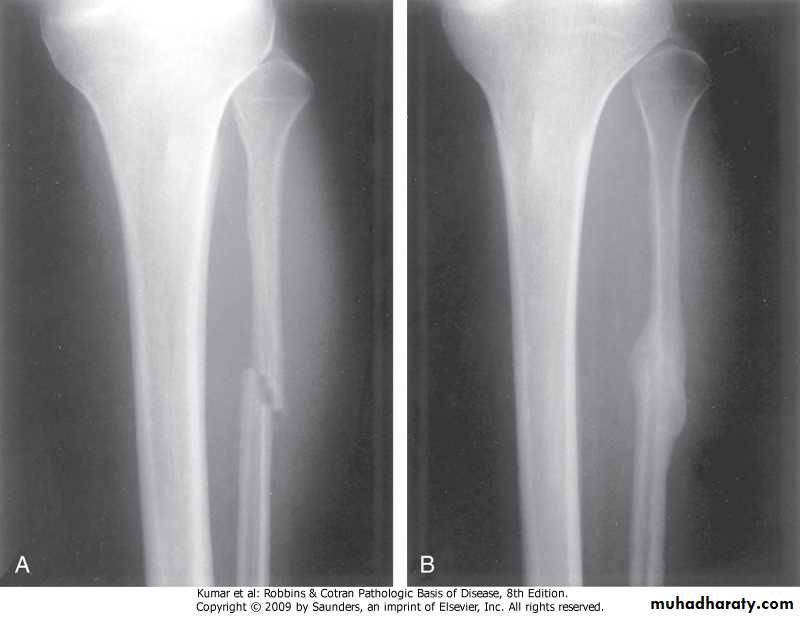

FRACTURES: fracture is defined as loss of bone integrity resulting from mechanical injury and/or diminished bone strength. either complete or incomplete; simple or compound; comminuted (splintered bone); or displaced .complications: -delayed union -nonunionFibula, fracture &callus formation